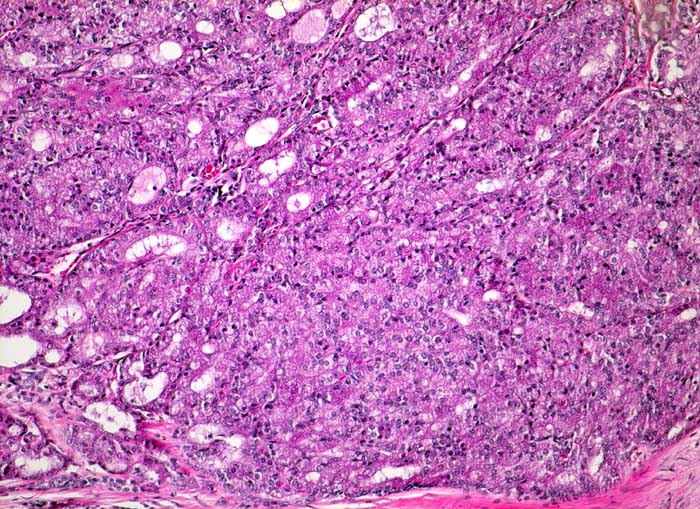

Azinuszellkarzinom der Parotis

Azinär differenzierte Tumorzellen mit reichlich wolkigem feingranulärem bzw. retikulärem Zytoplasma. Teils solides, teils follikuläres Wachstumsmuster.

Tumorzellen fokal Amylase und Diastase-PAS positiv

Azinuszellkarzinome sind nach den Mucoepidermoidkarzinomen und den nicht näher spezifizierten Adenokarzinomen die häufigsten malignen Speicheldrüsentumoren und am häufigsten bilateral (3%). Azinär differenzierte Zellen können oft nur eine Minderheit ausmachen. Daneben gibt es auch kubische Zellen vom Streifstücktyp oder Zellen eines Adenokarzinoms ohne spezielle Differenzierung. Azinuszellkarzinome können viele Wachstumsmuster zeigen: mikrozystisch, solide, follikulär, papillär zystisch, glandulär. Typisch, aber nicht spezifisch ist ein ausgeprägtes lymphoides Stroma (keine echten Lymphknoten), welches zur richtigen Diagnose führen kann. Die Azinuszellen enthalten Diastase PAS positives Material und sind immunhistochemisch positiv für Amylase (oft nur herdförmig).

Histologie

100